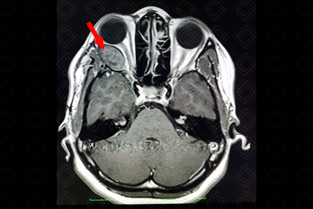

Texto alternativo para a imagem Figura 1. Créditos: Dra. Elazir Mota - Rio de Janeiro/RJ

Descrição da figura 1: Imagem axial ponderada em T1 evidenciando lesão ovalada, bem definida, com hipossinal estendendo-se do seio cavernoso à órbita (seta vermelha), com afilamento do músculo reto lateral, sugerindo schwannoma do VI par. Há desvio contralateral e suave do nervo óptico. [cms-watermark]

• Ressonância magnética do crânio: S ão heterogeneamente hiperintensos em T2. Nas imagens ponderadas em T1, são iso ou hipointensos, com ávido realce pelo meio de contraste. A clássica imagem do schwannoma é no ângulo pontocerebelar, pelo acometimento mais comum do VIII par (figuras 1, 2 e 3).